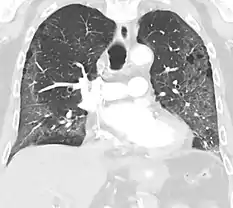

CT image showing crazy paving pattern of ground-glass opacities in both lungs.

Crazy paving

The crazy paving pattern may occur when there is both interlobular and intralobular widening. This sometimes resembles a road paved with irregular bricks or tiles. It is typically diffuse, involving larger areas of one or multiple lobes. There are a variety of potential causes, including Pneumocystis pneumonia, late-stage adenocarcinoma, pulmonary edema, some types of idiopathic interstitial pneumonias, diffuse alveolar hemorrhage, sarcoidosis, and pulmonary alveolar proteinosis.[6] COVID-19 has also been shown to occasionally cause GGOs with a crazy paving pattern.[11]